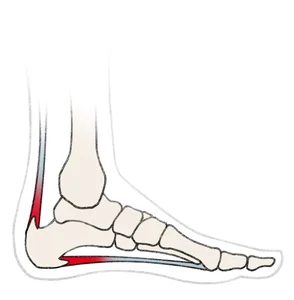

A heel spur is a sharp bony outgrowth of the heel bone (calcaneal tuberosity), the big bone inside your heel. Two important tendons are connected to the heel bone: the Achilles tendon and the plantar fascia, which runs along the sole of the foot. If the body is exposed to excessive stress, it can react by building up calcium deposits at the tendon insertion. Your body is essentially trying to stabilise the structures affected. However, these calcium deposits can also cause inflammation.

A heel spur usually occurs under the sole of the foot, at the insertion of the plantar fascia (called ‘plantar heel spur’). This heel spur can occur together with an inflammation of the plantar fascia, called plantar fasciitis, or it might even trigger it. A heel spur at the Achilles heel insertion is rather rare. A particularly rare condition is Haglund’s deformity. As opposed to the heel spur, this is a bone spur of the heel bone that covers a wide area.